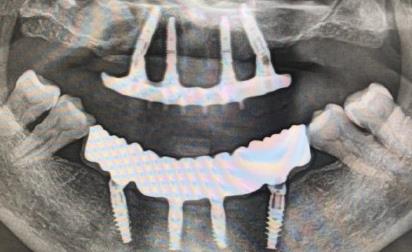

一般判斷是否能夠做種植牙都是需要經姑婆拍片後專(zhuan) 業(ye) 綜合評估的,因此建議**能夠具體(ti) 到醫院拍片查看一下牙齒缺失的情況,然後再詳細的谘詢醫生比較好。如果是牙槽骨條件滿足就可以做。

通過拍片可以查看牙槽骨的寬度和高度,如果滿足種植牙的條件,則可以做,如果不滿足,則一般需要創造條件,看能否通過植骨手術來彌補牙槽骨的不足。還有牙周的條件也重要,因為(wei) 牙周條件不好就會(hui) 直接影響種植牙的穩定性,所以如果有嚴(yan) 重的牙周病,或者嚴(yan) 重的牙齒鬆動、牙齦萎縮等情況,醫生是需要酌情考慮的。